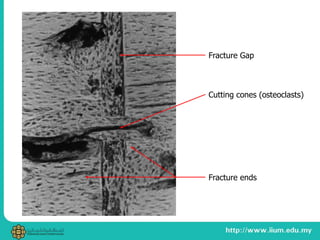

PRIMARY BONE HEALING

1. Immobilized fragments (no callus stimulus)

2. Gap healing – osteoblastic activity across

fracture to achieve contact healing

3. Cutting cones – remodeling action by osteoclasts

4. Relies on fixation for strength (no callus) and

may lead to osteoporotic changes of bone

Cutting cones (osteoclasts)

Fracture Gap

Fracture ends

PRIMARY BONE HEALING 1.Immobilized fragments (no callus stimulus) 2. Gap healing – osteoblastic activity across fracture to achieve contact healing 3. Cutting cones – remodeling action by osteoclasts 4. Relies on fixation for strength (no callus) and may lead to osteoporotic changes of bone

• #26 Gap invaded by capillaries and osteoprogenitor cells Less than 200 microM, osteogen produces lamellar bone straight away Bigger gap has woven bone laid down, which then remodels